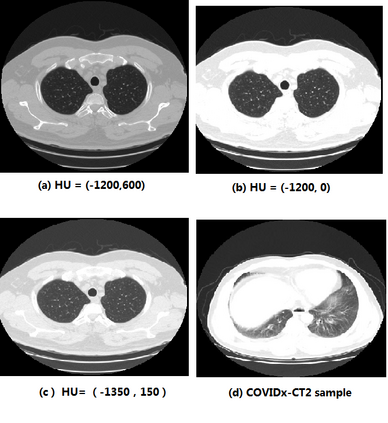

We present an automatic COVID1-19 diagnosis framework from lung CT images. The focus is on signal processing and classification on small datasets with efforts putting into exploring data preparation and augmentation to improve the generalization capability of the 2D CNN classification models. We propose a unique and effective data augmentation method using multiple Hounsfield Unit (HU) normalization windows. In addition, the original slice image is cropped to exclude background, and a filter is applied to filter out closed-lung images. For the classification network, we choose to use 2D Densenet and Xception with the feature pyramid network (FPN). To further improve the classification accuracy, an ensemble of multiple CNN models and HU windows is used. On the training/validation dataset, we achieve a patient classification accuracy of 93.39%.